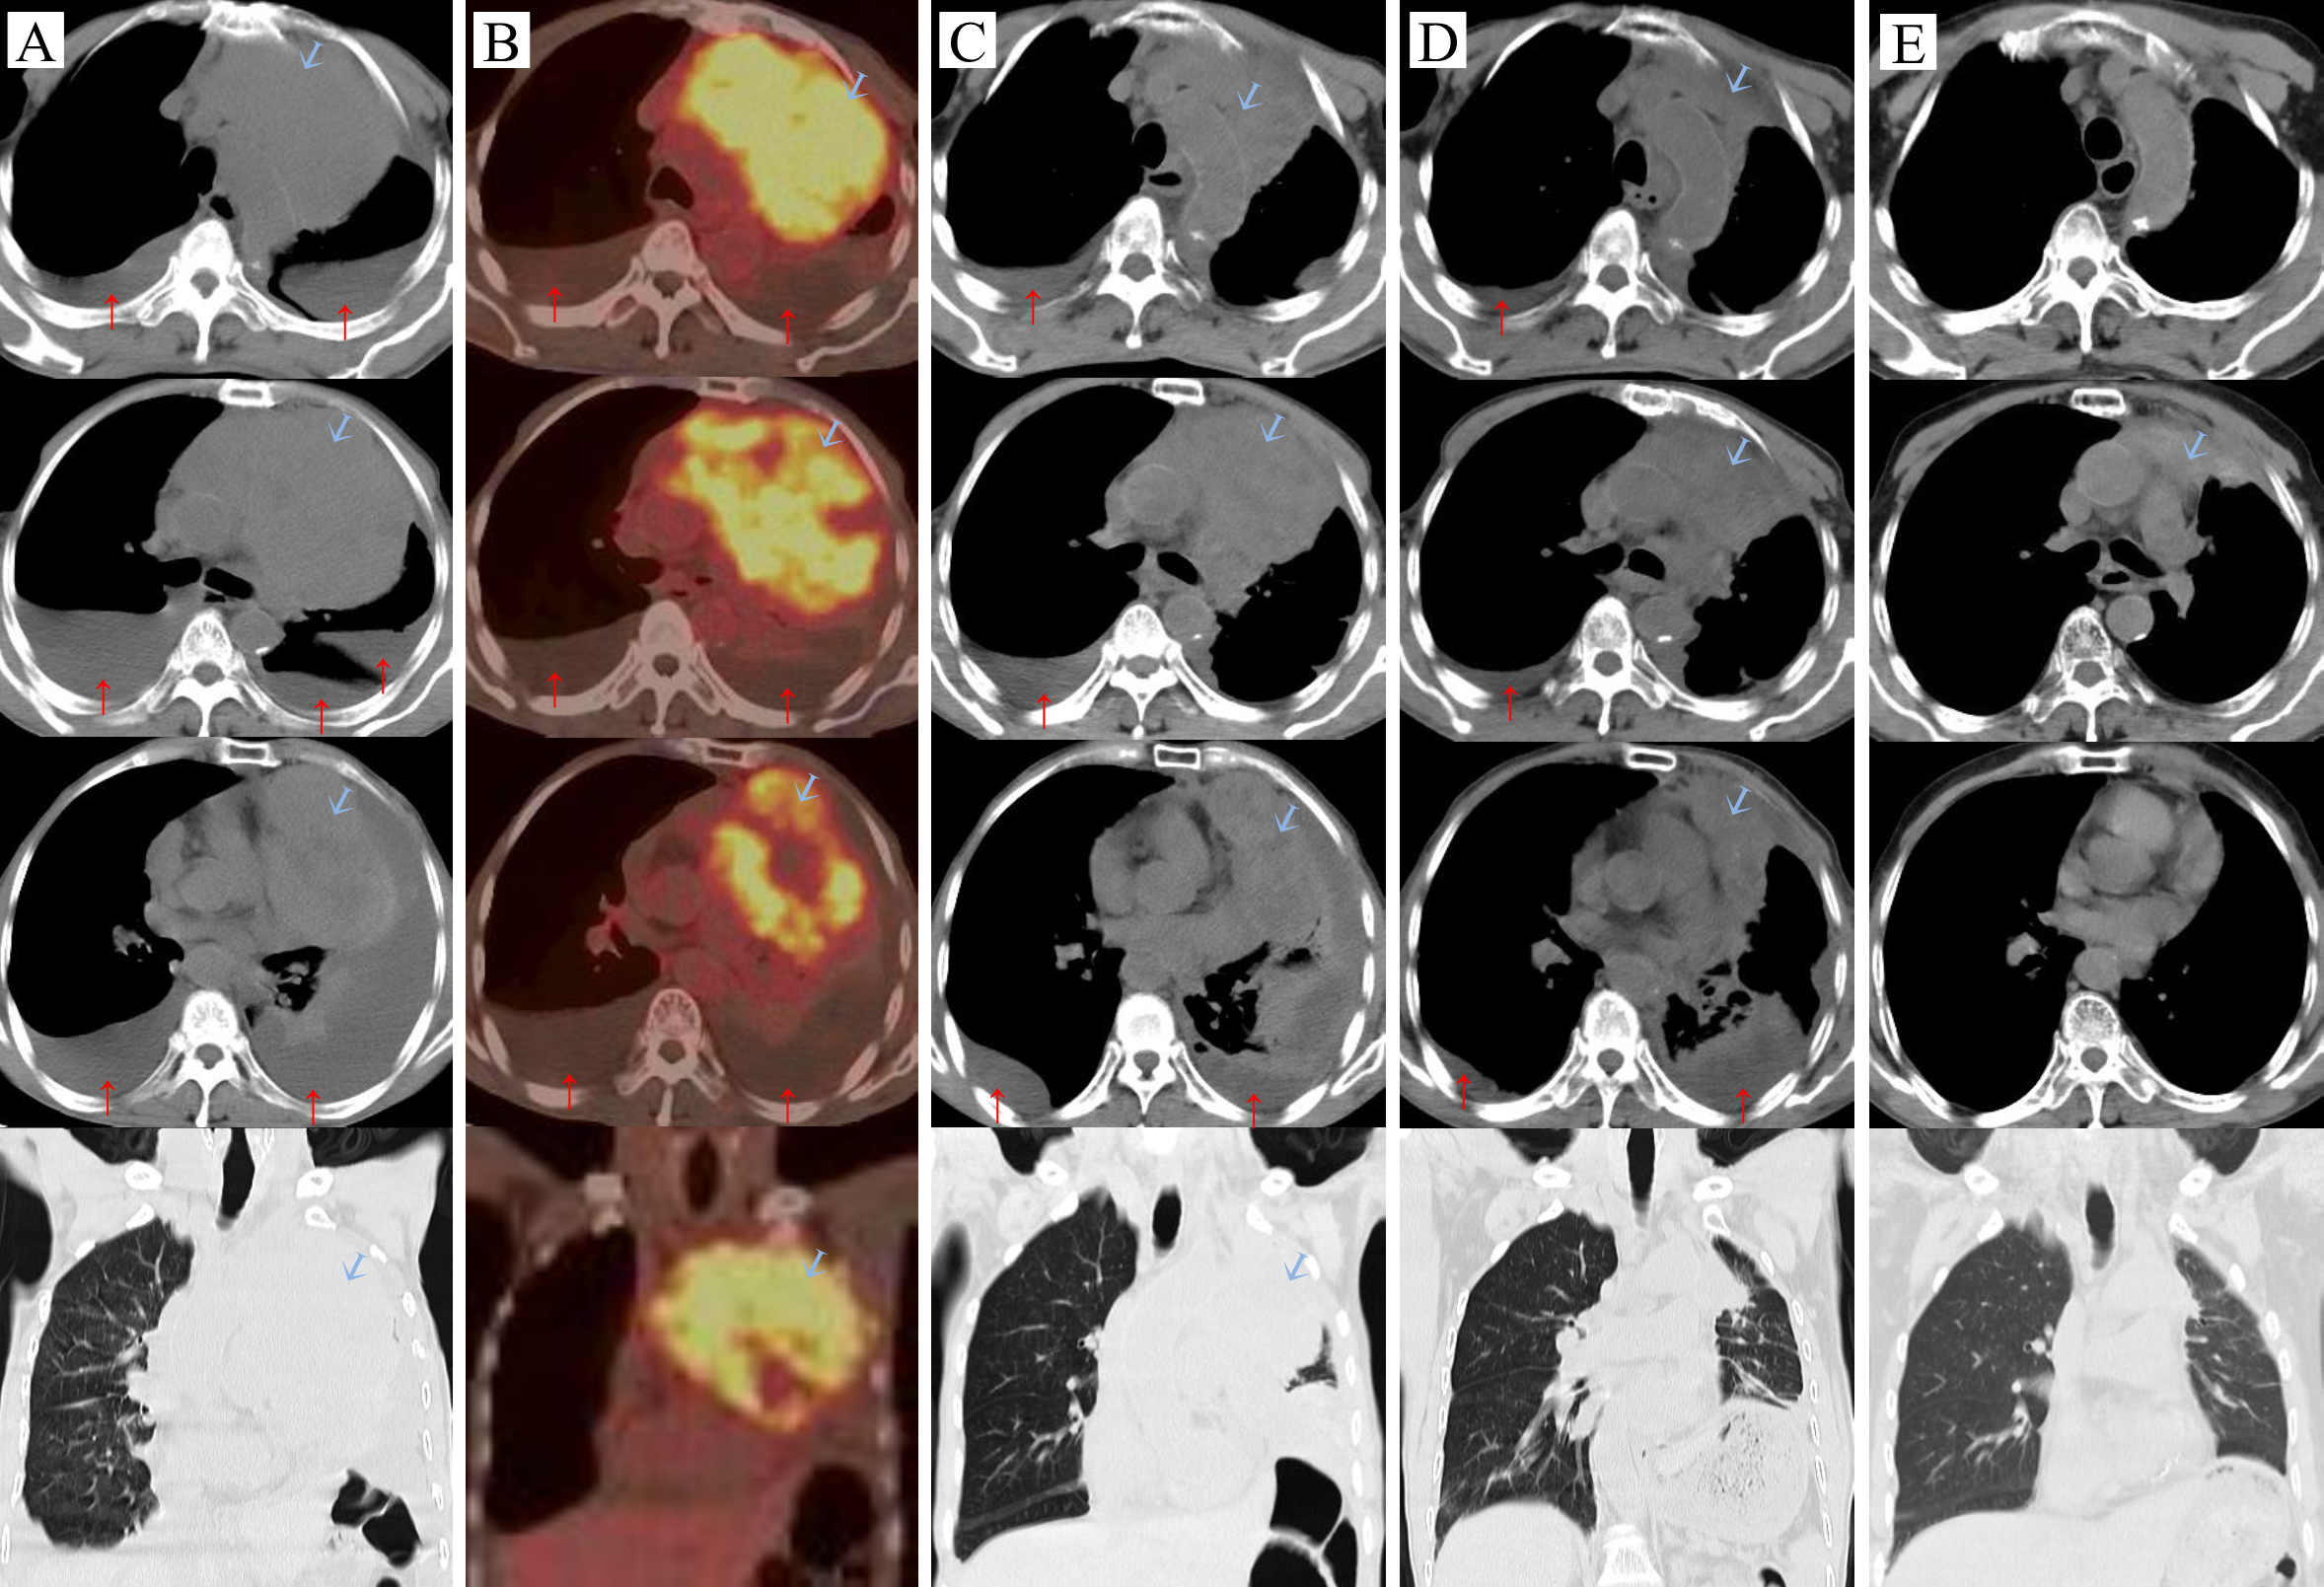

He was admitted in January 2023. A Physical examination revealed cachexia, a malnourished state, with distended left jugular veins, swelling of the left arm, absent breath sounds in the left lung, deviation of the trachea to the right, a heart rate of 130-145 beats per minute, a respiratory rate of 30-35 breaths per minute, and low blood oxygen saturation (88-91%) while on room air. Additionally, various blood parameters were abnormal (Table 1). Chest compute tomography (CT) scans showed a huge mass (13.9 cm×9.2 cm) in the anterior superior mediastinum (Figures 1A, 2A), accompanied by elevated left diaphragm, bilateral pleural effusion, pericardial effusion, and enlarged mediastinal lymph nodes (Figure 1A). There was also bony destruction of the left 2nd to 4th ribs near the sternum and the left side of the sternum. A Positron emission tomography/Compute tomography (PET/CT) scan further revealed intense 18F-fluorodeoxyglucose uptake in the mass and lymph nodes (Figure 1B). Furthermore, vascular ultrasound and CT angiography demonstrated multiple venous thromboses. CT-guided biopsy and immunohistochemical analysis showed the following results: CD117(+), CD20(-), CD3(-), CD30(-), CD5(+), CD56 (focal+), CK19(+), CK5/6(+), CK7(-), CK8/18(+), CR (focal+), PAX-5(-), KI67(+15%), OCT3/4(-), P63(+), PAX-8(-), Syn(-), TTF-1(-), TDT(-), and WT-1. Based on cell morphology, along with positive CD117(+) and CD5(+) and negative TTF-1(-), lung squamous cell carcinoma was ruled out, leading to a diagnosis of TSCC (7, 8). According to the Masaoka-Koga staging system, the patient was diagnosed with stage IVb TSCC (T4N2M1b) and a performance status (PS) of 4. Concurrent diagnoses included lung infection, respiratory failure, cachexia, anemia, hypoproteinemia, deep venous thrombosis, and chronic bronchitis. Given the patient’s large tumor, bilateral malignant pleural effusion, and dyspnea, his initial prognosis was poor, with an expected survival of less than two months.

Figure 1

Carcinoma changes:

tumor, ↑pleural effusion. (A) Before the treatment (2023-01-09), (B) On the day of the first intravenous infusion of Paberizumab, PET/CT scan (2023-01-19), (C) After the first cycle of antitumor therapy (2023-02-09): carboplatin + ABP + Pembrolizumab, (D) Third cycle of carboplatin + ABP + Pembrolizumab (2023-03-27), (E) Fourteen months later (2024-03-26).

During the treatment process, as the tumor shrank and the pleural effusion decreased (Figures 1C, D) the patient’s dyspnea gradually resolved, and his physical strength improved while his weight slowly increased, PS has gradually recovered (Figure 3). At the end of the seventh course, the pleural effusion had completely disappeared. The main side effects of chemotherapy were bone marrow suppression and gastrointestinal reactions. During the third and fourth courses, when the pleural effusion was reduced, he experienced a fever for one day after the intrapleural injection (IPI) of carboplatin, which resolved on its own. However, after the intravenous infusion, he had a fever for 3 to 4 days and required symptomatic treatment. Nevertheless, due to the effectiveness of carboplatin in reducing pleural effusion, it was not replaced. Anticoagulation therapy was also administered concurrently. Based on changes in the patient’s hemoptysis and bloody pleural effusion, the dose of low-molecular-weight heparin was increased from 2,500 U once daily to 5,000 U every 12 hours and then gradually reduced until the end of radiotherapy (Figure 3). The patient’s left jugular vein returned to normal, and the swelling in his left arm disappeared. Ultrasound showed that his left jugular vein and left subclavian vein were recanalized, although there was thrombosis in the left innominate vein.

After completing chemotherapy and ten cycles of pembrolizumab treatment, the patient discontinued pembrolizumab and underwent radiotherapy for the mediastinal lesion (200 cGy×30) and lymph nodes (200 cGy×25). Five weeks later, the patient experienced no discomfort, and all blood tests were normal. Therefore, pembrolizumab maintenance therapy was resumed (Figure 3). In both the February 2024 enhanced CT reconstruction and the March 2024 CT scan, it showed that the largest cross-sectional dimension of the tumor was 6.3 cm × 3.0 cm, and there was no recurrence of pleural effusion (Figures 1E, 2B). However, CT scans of the lungs revealed mild interstitial changes in the left upper lobe near the tumor. We extended the interval between pembrolizumab treatments. As of the revision of this article in December 2024, imaging examinations show no new tumor metastasis or pleural effusion, and the blood test results are normal. He has maintained a good quality of life for over 23 months, with a PS of 0.